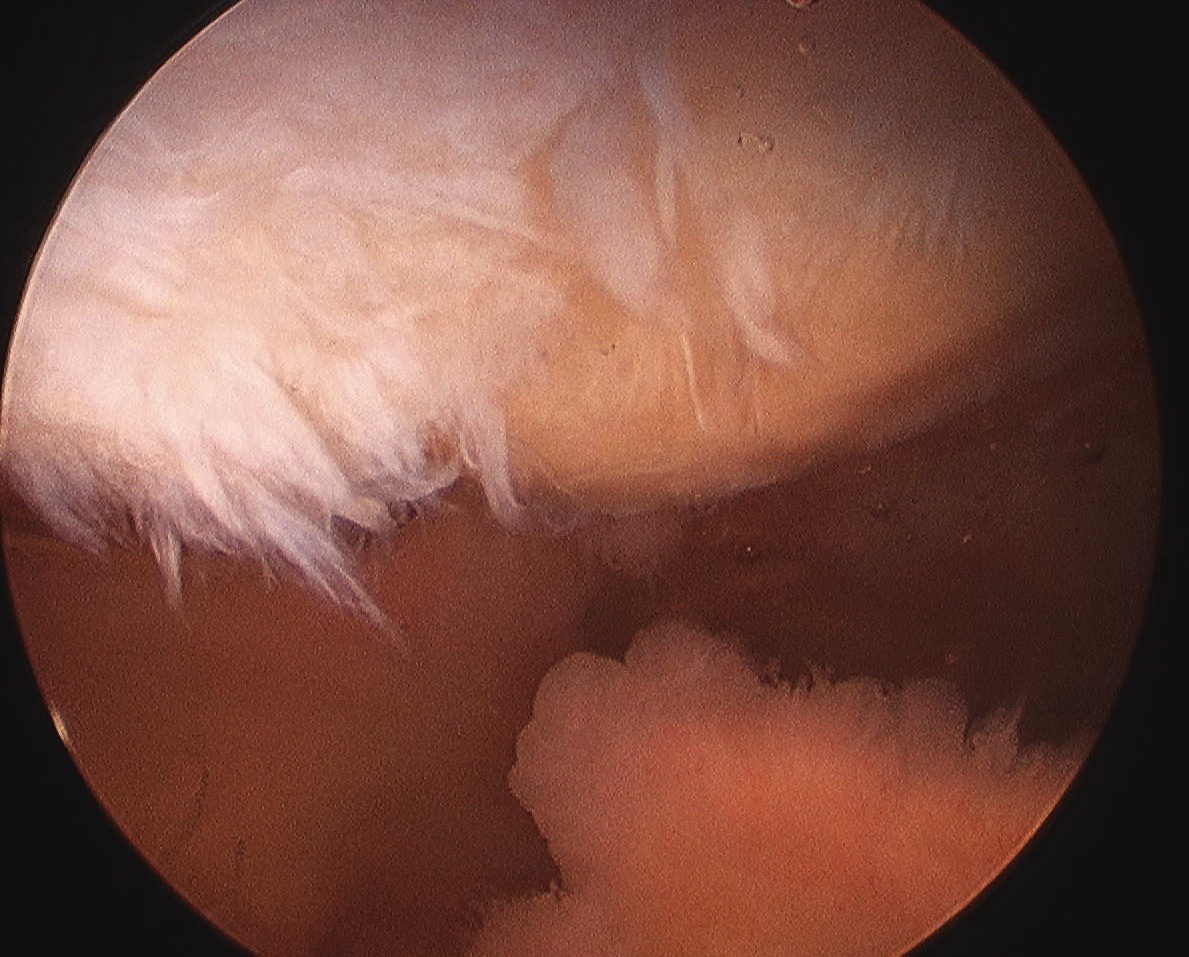

Arthroscopy

Patterns

Lateral facet - patella maltracking / trochlea dysplasia

Medial facet - patella dislocation and cartilage damage

Global - primary OA, patella fracture, obesity

Central trochlea - repetitive deep flexion

Medial facet OA Lateral facet OA